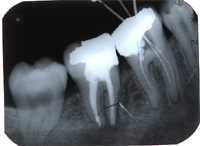

Ein 32 Jahre alter Mann kommt im November 1984 mit Zahnweh am unteren linken, zweithintersten Molaren (Backenzahn) in die Praxis. Das Röntgenbild von Abb. 1 zeigt insuffiziente Wurzelfüllungen bei allen drei Wurzelkanälen und an den Wurzelspitzen sogenannte Granulome, sichtbar als schwarze Flecken (grüne Pfeile in Abb. 1).

In Abb. 2 ist das Röntgenbild 22 Jahre nach korrekter Wurzelbehandlung mit dem nun überkronten Zahn zu sehen. Der Knochen um die Wurzelspitzen ist entzündungsfrei gesund.